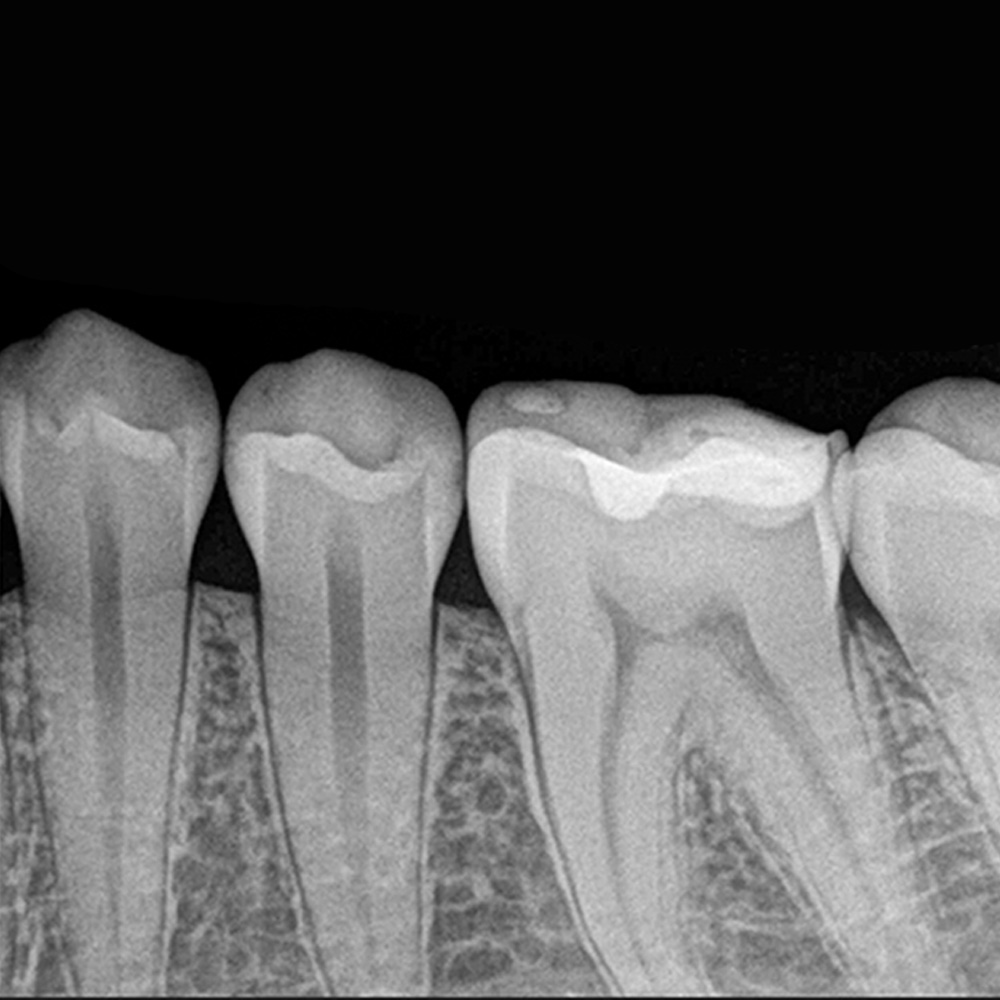

Radiografia sectorială este o radiografie dentară de mică dimensiune care surprinde un singur dinte sau un grup restrâns de dinți. Este utilizată pentru examinarea detaliată a unor zone specifice ale cavității orale, atunci când medicul are nevoie de informații precise despre un anumit dinte, o rădăcină sau o leziune.

Ce arată radiografia sectorială?

1. Structura internă a dintelui

carii dentare incipiente sau avansate

fracturi coronare și radiculare

obturații vechi și gradul lor de adaptare

2. Rădăcinile și zona periapicală

infecții la vârful rădăcinii

chisturi sau granuloame

resorbții interne sau externe